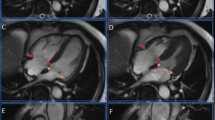

Results of LV volume and global functional measurements for the entire study cohort are summarised in Table 1. No significant differences were observed between end-diastolic volumes (EDV), end-systolic volumes (ESV), stroke volumes (SV), left ventricular ejection fractions (EF), or left ventricular muscle mass (MM) derived from the two gating approaches (Table 1). Volumetric data derived from the PCG-gated imaging approach showed excellent correlation with the volumetric data from the standard ECG-gated cine imaging approach for all variables analysed as demonstrated in the Passing–Bablok regression charts (Figs. 3a–e). Bland–Altman plots demonstrated excellent agreement between the results derived from both gating approaches (Figs. 3f–j). Regional wall motion abnormalities were observed in 34 patients in a total of 119 segments when evaluating the ECG-gated datasets, and in 33 patients in a total of 115 segments (P = 0.3652) when evaluating the PCG-gated datasets (Table 2). Evaluation of the short-axis sequences for gating artefacts per patient revealed a mean percentage of cine short-axis images with gating artefacts of 8.78 ± 13.38% (range 0% to 47%) for the ECG-gating approach and of 13.85 ± 17.79% (range 0% to 70%) for the PCG-gating approach (P = 0.0059); however, in the majority of cases excellent image quality was observed with both gating approaches (Fig. 4). To guarantee diagnostic quality of each dataset, 30 ECG-gated short-axis sequences and 36 PCG-gated short-axis sequences (P = 0.4832) had to be repeated (Fig. 5). Physiological and pathological characteristics of patients with gating artefacts in the cine SSFP datasets and of patients in whom repetition of cine slices had been necessary are given in Table 3.

Mid-ventricular short-axis cine SSFP MR images of a 60-year-old male patient with suspected coronary heart disease acquired twice with PCG gating: whereas the initial acquired image (a) shows gating artefacts particularly at the lateral wall of the left ventricle, the repeated image (b) shows a good image quality without gating artefacts